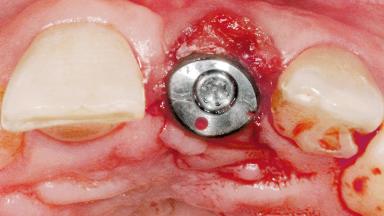

Late Flapless Placement of an Implant in a Maxillary Left Central Incisor Site

A 39-year-old male patient presented with a chief complaint of discomfort and gingival discoloration around his maxillary left central incisor. He was in good general health and was a non-smoker. His past dental history was significant because of the traumatic fracture of tooth 21 in a sporting accident at age 13. Initial dental treatment included endodontic therapy and a full-coverage restoration. The patient became symptomatic 5 years later, when structural failure of the tooth resulted in the dislodgment of the crown. Endodontic retreatment, apical surgery, and post-and-core restoration were performed.

Soft Tissue Grafting Simultaneous

Abutment Type Standard

Prosthesis Type FDP

Soft Tissue Contour and Volume Slightly compromised